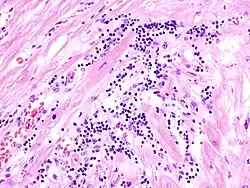

Mikro: Interstitielles lymphozytäres Infiltrat (kleine blaue Zellen), kaum Nekrosen.

Mikro: Granulomatöse Entzündung, ASCHOFF Knötchen perivasal (ASCHOFF Riesenzellen: Große, ein- oder mehrkernige Zellen mit prominenten Nukleolen), ANITSCHKOW Myozyten: Lange dünne Zelle mit elongiertem Kern.